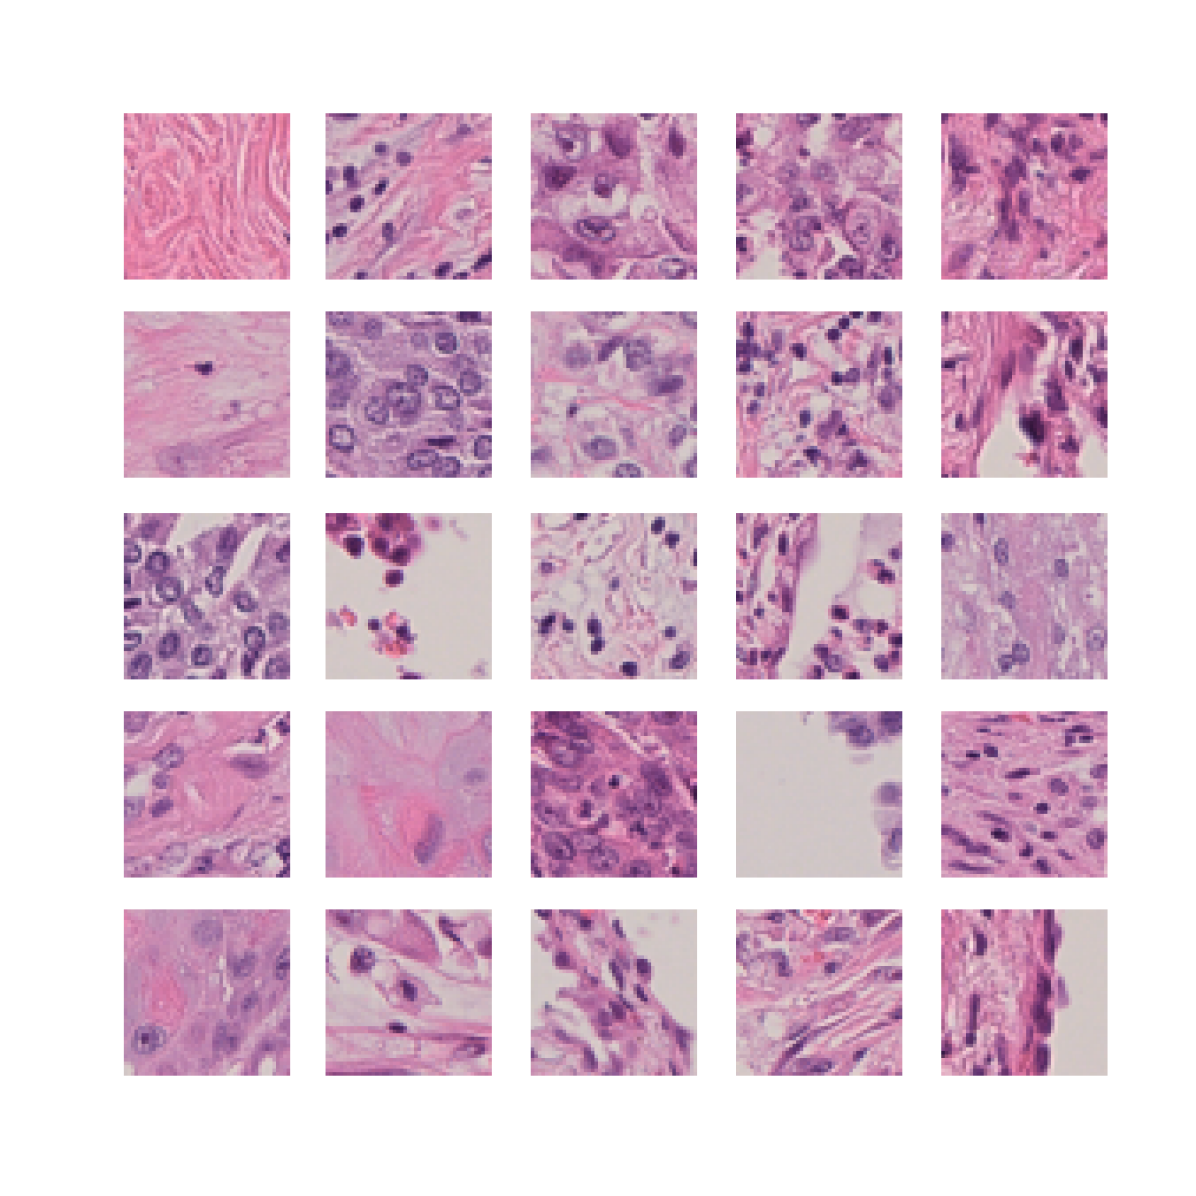

We also analyse the activation maps for each model using GradCAM as described in section S3. This offers more insight into the areas of the image which are contributing most heavily to the models’ representations. In Figure 4(b) we present some representative examples, however, a larger selection which was chosen at random is presented in Figures S10 to S25. The larger selection makes it easier to see the emergent patterns, including that privileged Siamese models tend to mainly identify features which are strongly present in both inputs, while unprivileged Siamese models tend to learn more diffuse features that are not specific to one cell phenotype or image region. TriDeNT ♆ incorporates both sets of features, learning both features specific to the privileged data and more the general features associated with unprivileged Siamese networks.

We can see in Figure 4(b) panel A that for ERG, the privileged Siamese model focuses almost exclusively on any nuclei which could be endothelial cells. As there are very few endothelial cells in the dataset, it could be an effective strategy to identify anything that could potentially be an endothelial cell to minimise the difference between the representations of the H&E model and the IF mask model. In the corresponding unprivileged Siamese image, we see that the model identifies some of these nuclei, albeit less strongly, but also focuses heavily on the other tissue and even the background, while strongly fixating on two spots of debris in the center of the image. This model has less ‘incentive’ to learn the weak features related to endothelial cells as these occur rarely and are not easy to detect, while more generic strong features such as the presence of connective tissue and the prevalence of background are more common and predictable from augmented images. We see that TriDeNT ♆ combines these two feature sets, strongly identifying nuclei while also identifying the connective tissue.

In panel C we see a similar pattern, with the privileged Siamese model fixating solely on the nuclei, while the TriDeNT ♆ model takes a more balanced approach. The unprivileged Siamese model appears to focus on a single cluster of nuclei while neglecting others, and similarly identifies an area of fibroblasts with its distinctive pattern but does not others.

In contrast to panels A and C which represent models with poor privileged Siamese results, panels B and D represent models whose privileged Siamese results were comparable to both TriDeNT ♆ and even the supervised baseline. It is therefore interesting to note that there are far more similarities between the privileged Siamese and TriDeNT ♆ models in both cases. Particularly in panel B, TriDeNT ♆ and the privileged Siamese model return virtually identical heatmaps, with both strongly identifying epithelial nuclei and neglecting the same areas of connective tissue. The unprivileged model in this case appears to focus solely on the centre of the image, giving a significantly different heatmap to the other panels.

Panel D again shows the previous pattern, with the privileged Siamese model identifying the features strongly present in the privileged data – fibroblasts – while neglecting the nuclei present. TriDeNT ♆ also strongly identifies the connective tissue, but, unlike the privileged Siamese model, does not completely neglect the nuclei. The unprivileged Siamese model primarily identifies background, and does not appear to identify the nuclei in this example.